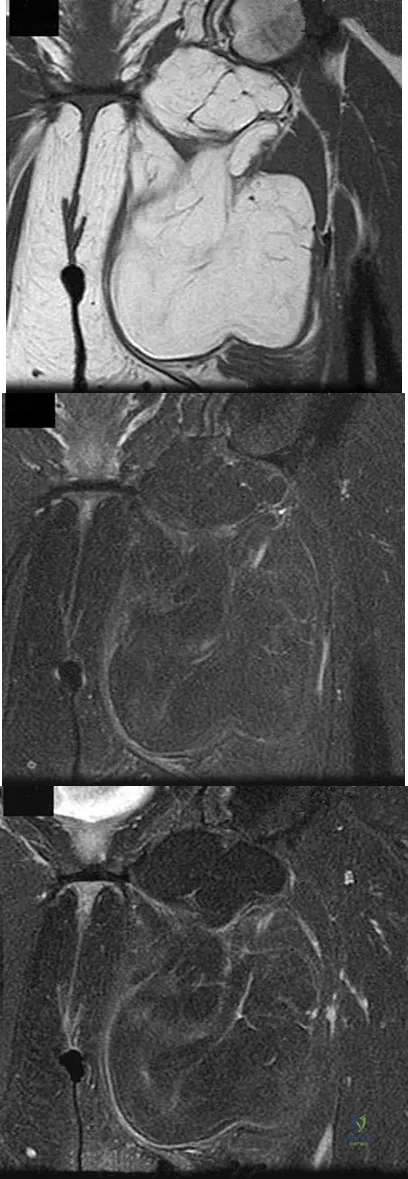

Figures 24a through 24c show the coronal T1-weighted, T2-weighted fat-saturated, and T1-weighted fat-saturated gadolinium MRI scans of the proximal thigh of a 52-year-old woman who reports a mass in the medial thigh and groin area. She notes that the fullness has grown in size over the course of many months. Based on these findings, what is the most likely diagnosis?